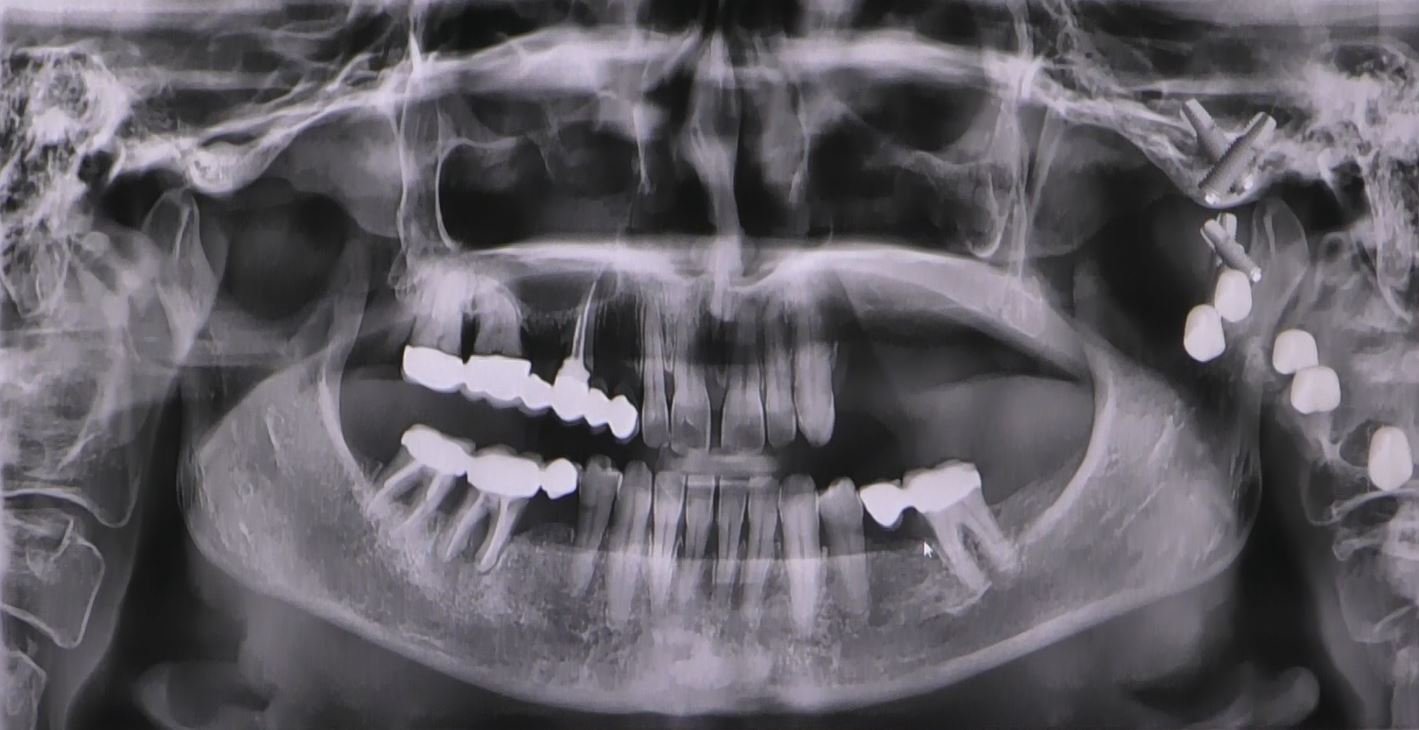

- Valutazione Radiografica: Una valutazione dettagliata ha fornito informazioni cruciali sulla quantità di osso disponibile e sulla strategia di posizionamento degli impianti.

Il nostro paziente, affetto da grave atrofia ossea mascellare, è stato selezionato per sottoporsi a questa procedura avanzata. La valutazione preoperatoria accurata ha guidato la pianificazione, assicurando che la tecnica fosse adattata alle specifiche esigenze anatomiche del paziente.